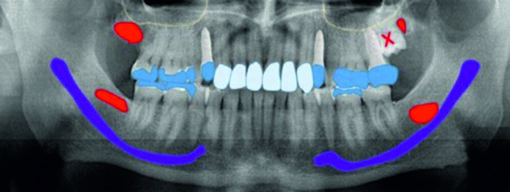

Hinweis: Sollten Sie bereits über eine aktuelle Panoramaschichtaufnahme verfügen, können Sie diese gerne vorab per E-Mail an uns schicken (info@biologische-zahnmedizin-kiel.de).